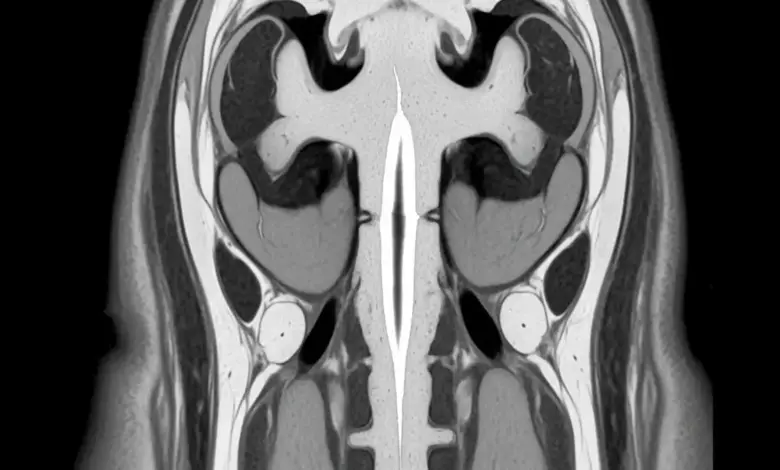

Siringomielia é uma alteração da medula espinhal em que surge uma espécie de cisto, cheio de líquido, dentro dessa estrutura.

A cavidade, chamada siringe, pode ocupar diferentes trechos da medula espinhal e comprimir ou irritar as fibras nervosas que passam por ali.

O exame de escolha para investigar siringomielia é a ressonância magnética da coluna, que permite visualizar a medula em detalhes. Com ela, o especialista consegue:

• Identificar a presença da siringe e suas dimensões.

• Localizar exatamente em quais segmentos da medula está a cavidade.

• Verificar se existe malformação de Chiari, tumores ou outras alterações associadas.